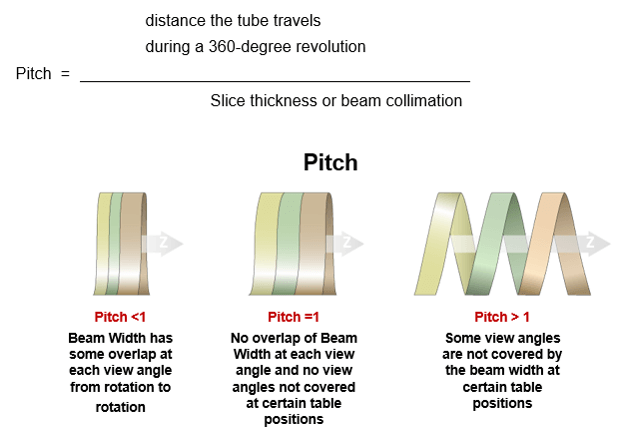

PITCH

Spiral pitch or helical pitch is defined as the ratio of the distance the table travels per rotation to the total collimated x-ray beamwidth. It can also be defined as an extension or contraction of the helix. The pitch has an inverse relationship to the dose. If the Pitch increases by 2, the dose is reduced to one half. It affects not only patient dose but image quality as well.